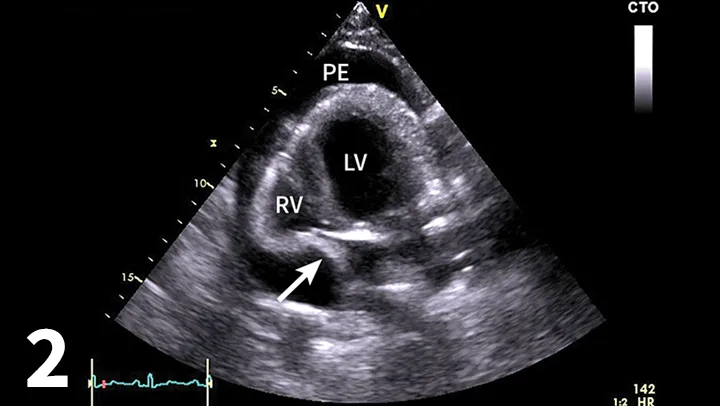

Figure 3

Right lateral thoracic radiograph for patient presenting with acute collapse. The heart is globoid while the pulmonary vasculature is small. The caudal vena cava is hard to visualize but would likely be dilated.

• Thoracic radiography

• The heart may be relatively normal (acute hemorrhage) or globoid (chronic effusion; Figure 3). Distention of the caudal vena cava, ± pleural effusion, ± peritoneal effusion, may also be present.